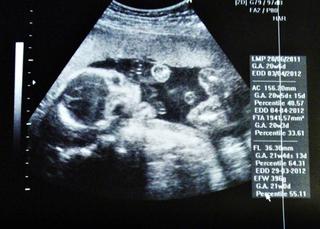

No ale toto som chcela: včera sme mali morfo sono...všetko super ako má byť...dokonca sa nám to naše malé drobča ukázalo a pán doktor povedal že vidí kávové zrnko🙂 s manželom sme sa usmiali a potom to ešte potrvdil, rýchlim 3D-čkom takže MÁME MALÚ PRINCEZNÚ V BRUŠKU !!! tešime sa moc...a dokonca vraj bude mať dlhé nohy, čo som ja vždy chcela, preto sa tešim eśte viac 🙂 Má takmer 400 g podľa počitača 🙂

Inak ak aj vy máte takéto snímky a neviete si rady so skratkami tak toto znamenajú :

BPD (priemer hlavy),

HC (obvod hlavy),

AD (priemer brucha),

AC (obvod brucha),

FL (dĺžka stehennej kosti).

G.A. (vek plodu podla meranej časti tela)

EDD (predpokladaný termín pôrodu)

len neviem co je ten percentil 🙂 vy viete?

Tu pridávam fotky našej krásavice a jej kávového zrnka 🙂